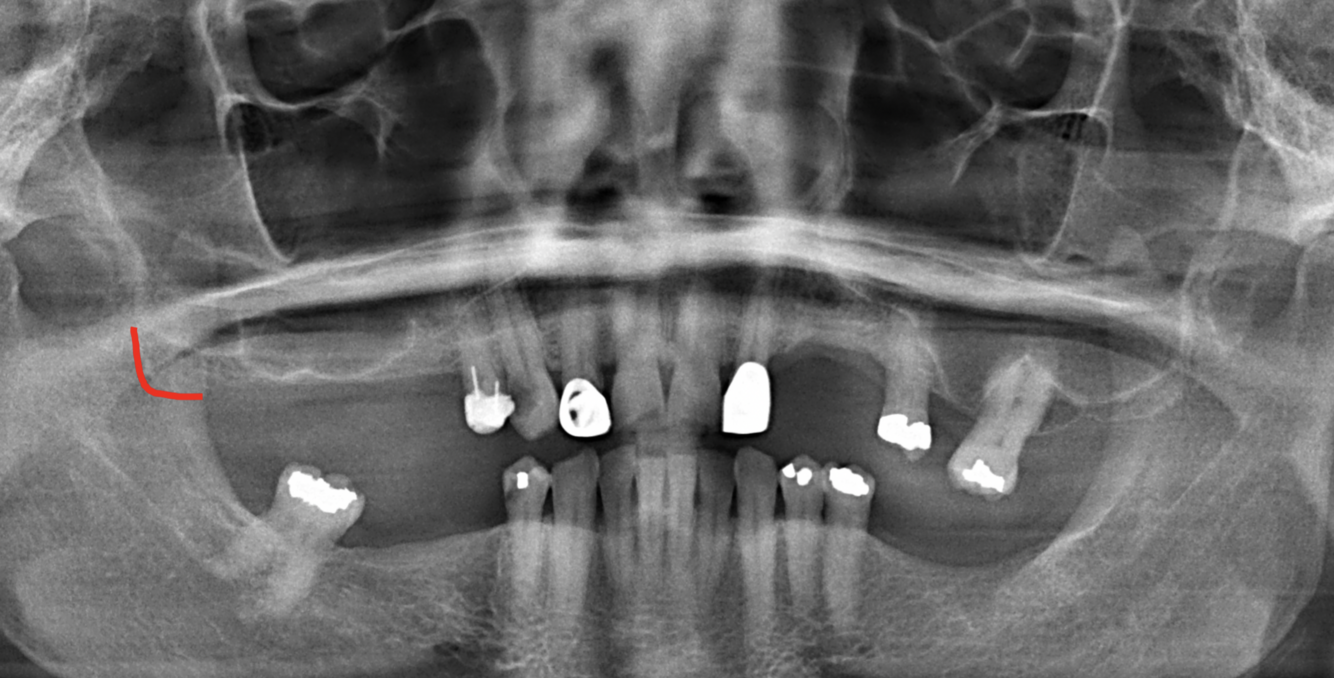

What does the red indicate in the following image?

Signmoid notch